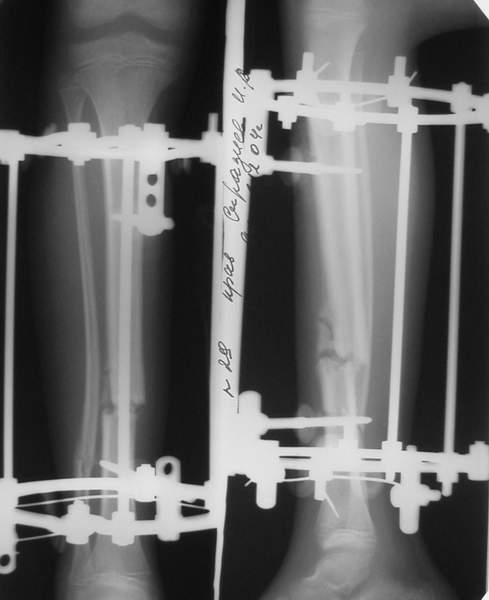

Под рукой прилагаемый пример. Как видите, "стриптиз-аппарат" (шутка проф. З.К.Башурова): 3 кольца-2 кольца-2 полукольца. В случае, который представил Евгений, характер повреждения позволил бы сразу использовать аппарат на основе 2 колец; в крайнем случае прокс. опора м.б. демонтирована сразу после репозиции.

В аттачтах №№ 1 и 2 - примеры, когда 2 кольца не позволили послеоперационно

исправить смещение фрагментов большеберцовой (по ширине и вальгусное).

А казалось бы (#2) - поиграй на штангах и все влетит.

Оперировал не я

1

1a